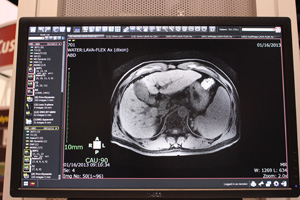

iIR(image-based Iterative Reconstruction)は,従来はCT本体でしか実行することができなかった逐次近似再構成を,ワークステーション側で応用する技術である。CTからワークステーションに取り込んだ画像データを順投影によりサイノグラムデータに戻し,その投影データに逐次近似画像再構成を応用して画像を再構成し直すという方法で,ノイズの少ない画像をポストプロセスで取得することができる。撮影画像のノイズを低減できるようになるため,撮影時の被ばく線量低減に貢献する。まずは被ばく線量が多いとされるCT Perfusionへの適応から開発が進められている。

逐次近似画像再構成が搭載されていないCTの画像に対して実行できるだけでなく,逐次近似画像再構成による画像に対しても同様の方法で実行することができるため,さらなるノイズ低減を図ることが期待される。iIRにより,逐次近似画像再構成が搭載されていないCT装置を使用している中小規模の病院やクリニック,低被ばく検査が求められる検診施設などでの利用が想定される。

iIRは,VirtualPlaceに搭載するソフトウェアとして提供するとともに,CTメーカーへのOEM供給も検討しているという。来春のITEM 2014での詳細な発表をめざして開発が進められている。